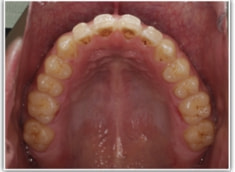

開咬(かいこう:オープンバイト)ケース

治療法:表の矯正(T21ブラケット)

(インプラントアンカーや外科矯正は行わず、エラスティックと機能訓練のみ)

治療後(2年2ヶ月後)